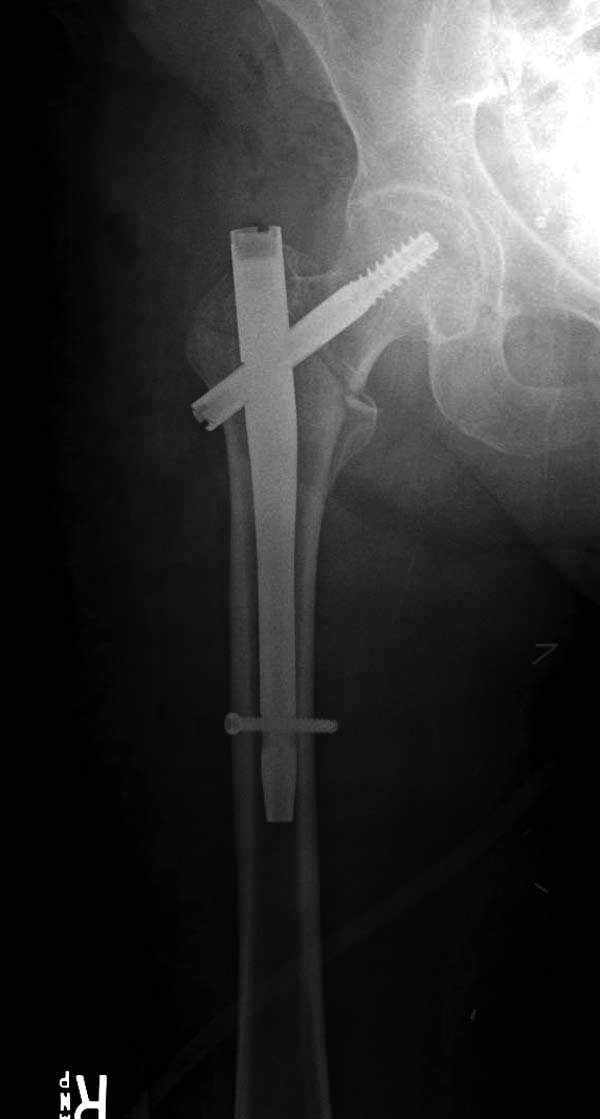

Такие “чужие осложнения” встречаются у всех и представляю банальный случай, который шаг за шагом показано как перерос в более сложный процесс... Больная 70 лет, множественные ко-морбидности, чрезвертельный перелом первоначально фиксирован Гамма 3. Осложнение в течение 6 недель, ревизия тотальной артропластикой и во время установки ножки обнаружена трещина диафиза (17), из малого доступа фиксация алло-графтом.

Обычно после чрезвертельных переломов, за исключением молодых, у пожилых остается нестабильность при движении. Часто падают и после 3х мес. в результате падения обнаружен перипротезный перелом (22-23), который зафиксирован Синтез пластиной.

Повторно поступает после двух с половиной лет, где обнаруживается перелом на второй стороне. Немного сложно, но для фиксации выбрали Antegrade InterTan Smith Nephew Nail и с момента фиксации более 3х мес.